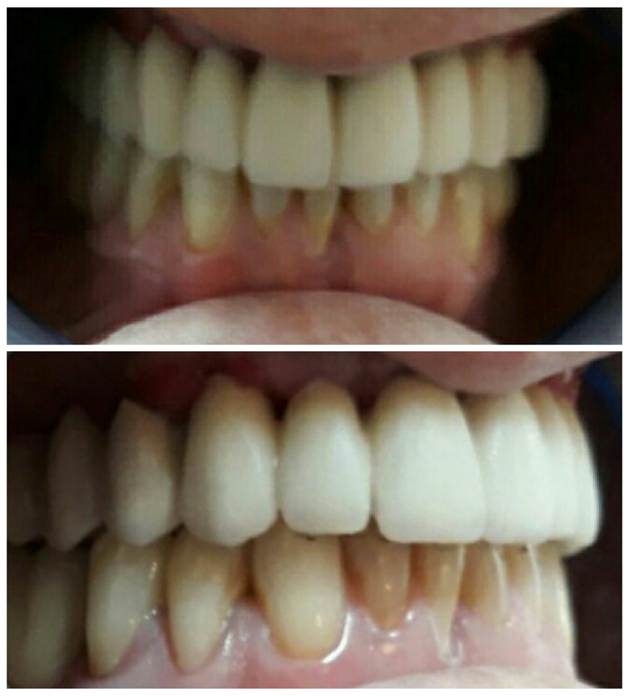

Se programa cirugía para la inserción de 7 implantes superiores para carga inmediata . El mismo día de la de la cirugía se toman las impresiones, que son enviadas a laboratorio. Procedemos a la fabricación de una prótesis híbrida provisional. 24 horas después de la cirugía, el paciente sale de la clínica con su prótesis superior atornillada . Esta prótesis será funcional durante todo el proceso de fabricación de la rehabilitación definitiva . En la fabricación vemos que la emergencia de 2 de los implantes anteriores es vestibular, lo cual nos exige angular al menos esos 2 pilares (11 y 13).. También nos alerta a nivel de estética ya que los dientes superiores apenas son visibles.

Comenzamos realizando un encerado diagnóstico, buscando estética y funcionalidad.El sector anterior se enfila teniendo en cuenta que la angulación de los pilares 11 y 13 no sea superior a 25º y bajando un poco la línea incisal para que los incisivos resulten más visibles. A nivel de 21-22 se observa un tramo de pérdida ósea por lo que valoramos con la doctora la opción de hacer soporte labial cerámico con estética rosa en dicho tramo. La prueba del encerado diagnóstico en boca nos confirma que no es necesario . La Dra. Mónica Paupie hace los retoques oclusales necesarios en clínica y con la conformidad del paciente damos por satisfactoria la prueba.

Una vez realizados los ajustes necesarios tanto en clínica como en laboratorio, procedemos a terminar la rehabilitación. En clínica se obturan los canales de emergencia con composite. El ajuste en mucosa es excelente y el paciente se muestra totalmente satisfecho tanto a nivel estético como funcional.

![]() | EN EL MOMENTO DE LA COLOCACIÓN. Se observan pequeñas lesiones e inflamación de la mucosa. |

![]() | UN MES DESPUÉS. Se puede observar en pocos días que comienza la desinflamación y readaptación de la encía. |